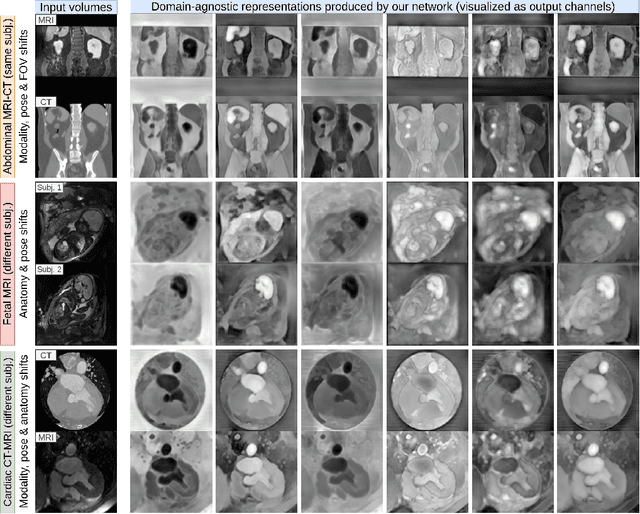

Abstract:Current volumetric biomedical foundation models struggle to generalize as public 3D datasets are small and do not cover the broad diversity of medical procedures, conditions, anatomical regions, and imaging protocols. We address this by creating a representation learning method that instead anticipates strong domain shifts at training time itself. We first propose a data engine that synthesizes highly variable training samples that enable generalization to new biomedical contexts. To then train a single 3D network for any voxel-level task, we develop a contrastive learning method that pretrains the network to be stable against nuisance imaging variation simulated by the data engine, a key inductive bias for generalization. This network's features can be used as robust representations of input images for downstream tasks and its weights provide a strong, dataset-agnostic initialization for finetuning on new datasets. As a result, we set new standards across both multimodality registration and few-shot segmentation, a first for any 3D biomedical vision model, all without (pre-)training on any existing dataset of real images.